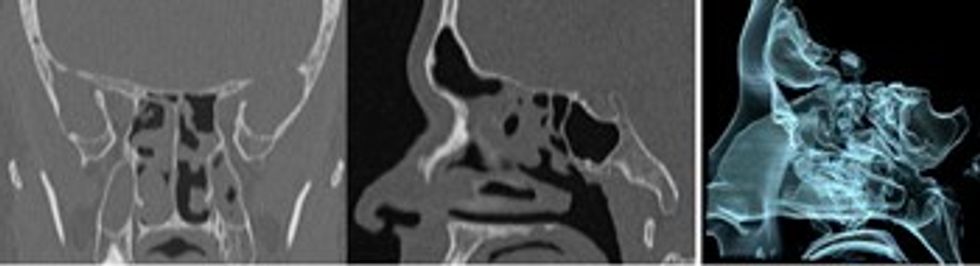

Hapësirat paranazale – sinuset mund të analizohen përmes rekonstruimeve në të tre rrafshet bile ndaras të paraqitet aerizimi i hapësirave paranazale.